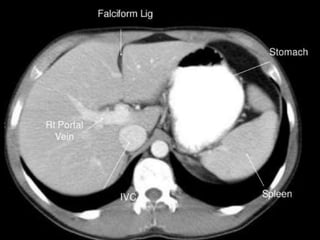

CT – computed tomography.

•Cross-sectional modality

with capabilities for

multiplanar reconstruction

and dynamic imaging to

assess vascularity

•Tube rotates around the

body and a circle of

stationary detectors detects

the penetrating x-rays

forming an image.

CT cross sectional anatomy.